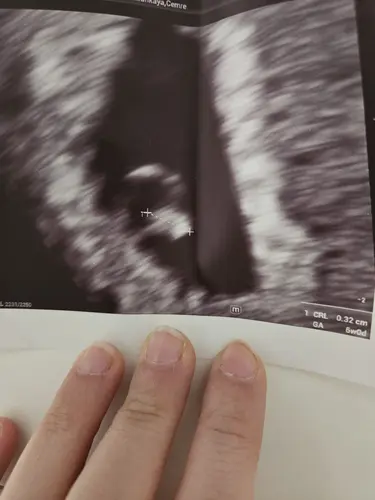

Das war bei mir 5+2

Und bei 6+0 das baby mit Herzschlag